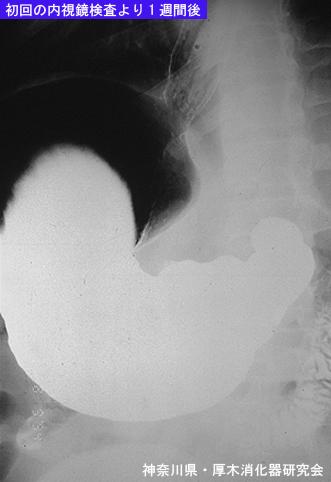

Posted by: Kanagawa Pref., 厚木消化器官研究会

疾病(病理主体)的分类寄生虫疾患/异尖线虫

检查方法X线